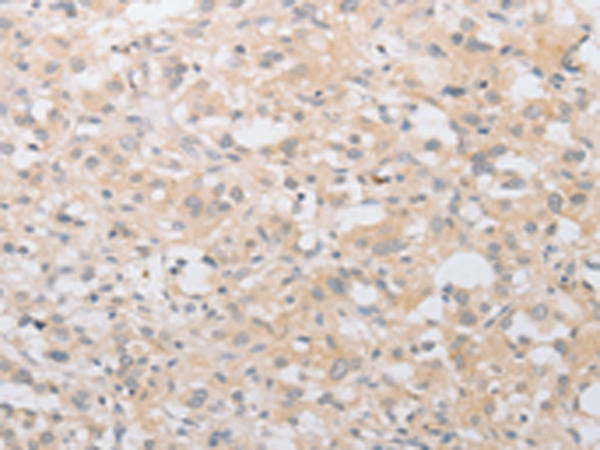

分类: 科研抗体货号: P08027别名: HNAC1; BCDase; LCDase; NCDase; N-CDase应用: WB,IHC反应种属: Human, Mouse, Rat